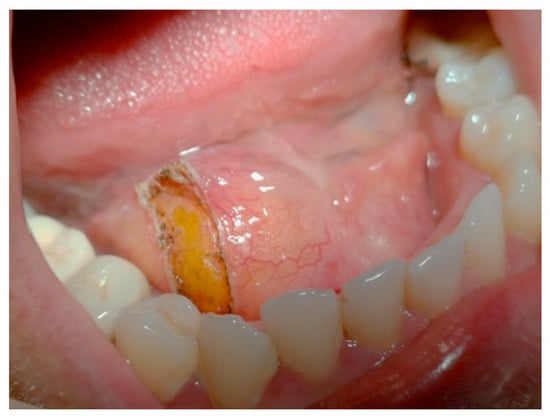

445 nm Blue Laser in Excisional Biopsy of a Large Lipoma of the Mouth Floor †